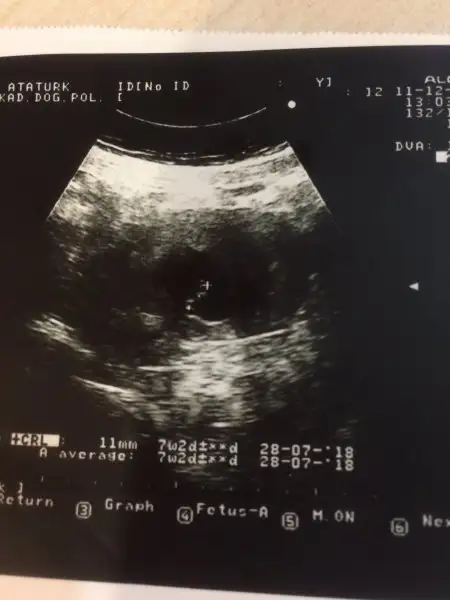

Canım bak ilk resimde kesenin etrafında beyaz bi yarım halka var ve çoğunlukla sol tarafta o halka plasenta bebeğin eşin yani pşasenta ne taraftaysa bebekte o tarafta oluyo yani bebek erkek gibi teoriye göre